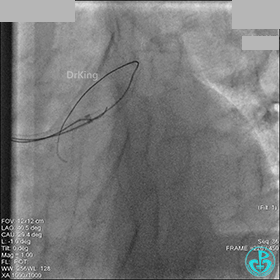

AL 1.0指引导管到位,简单短时尝试导丝不能顺利通过前降支或回旋支病变。改变策略处理右冠脉病变,计划植入2枚支架。AL指引导管到位,Sion blue导丝到达右冠脉远端。导丝通过后1.5mm及2.5mm球囊14~16atm充分扩张中段病变。

右冠脉中段充分扩张后欲植入3.5×38mm支架时,支架难以通过中远段扭曲处,且指引导管、导丝弹出飞扬。反复尝试导丝重新到达右冠脉远端时通过不顺利,局部造影剂滞留,远端血流接近3级。